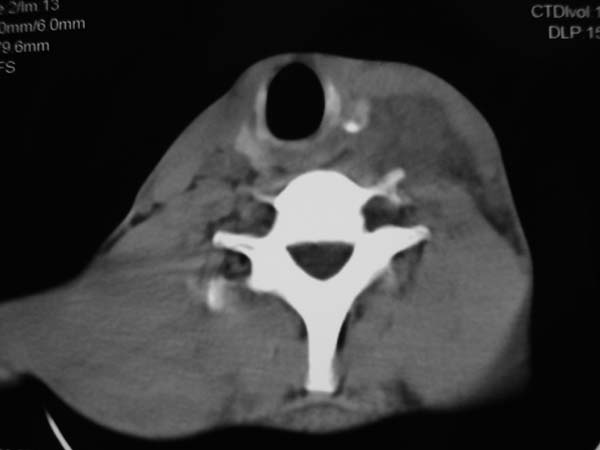

标题: CT7516[颌面颈部]:颈部病变,请会诊!

患者男性,37岁,农民,自觉左颈部肿大三天,无其它不适。

左侧颈部软组织密度肿块,界限清楚,形态不规则,占位效应明显。考虑:1 淋巴瘤。2 神经源性肿瘤不除外。

考虑神经源性肿瘤.

病灶边界较清,密度不均,其内可见坏死灶,左侧甲状腺受压,考虑神经源性肿瘤可能性大,建议穿刺活检。

支持左侧神经源性肿瘤。

病灶边界较清,密度不均,其内可见坏死灶,左侧甲状腺受压,考虑神经源性肿瘤可能性大。

考虑神经源性肿瘤可能性大,建议穿刺活检。